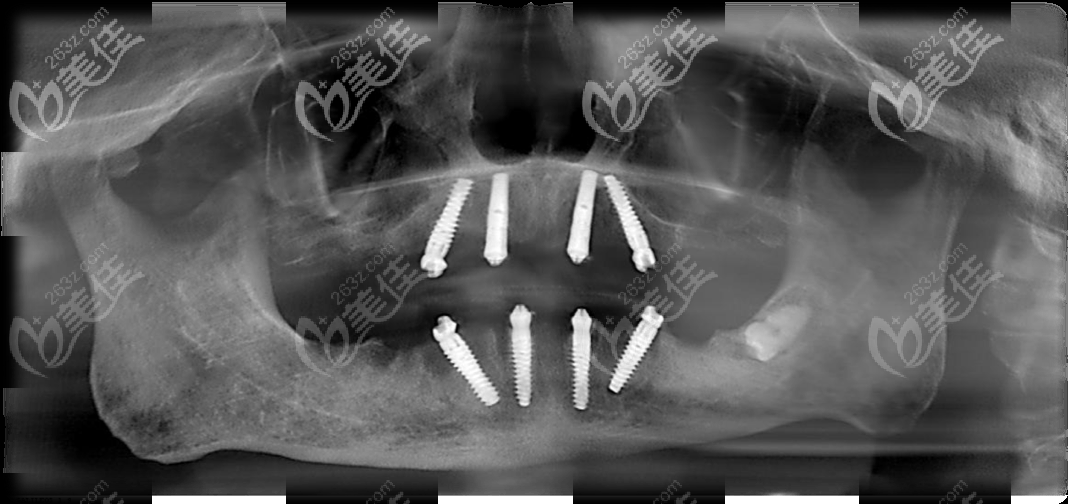

这张是做全口all-on-4种植牙后的CT片

林大爷在马泷齿科做的allon4全口种植牙,上下颌各用了4颗种植体;种完当天就能啃苹果哦!

所以,马泷的正院长建议做ALL-ON-4即刻负重种植牙,将两颗植体纯直植入、两颗植体倾斜植入,形成拱形受力,不用植骨,当天种牙、当天戴临时牙冠、当天吃东西~~~